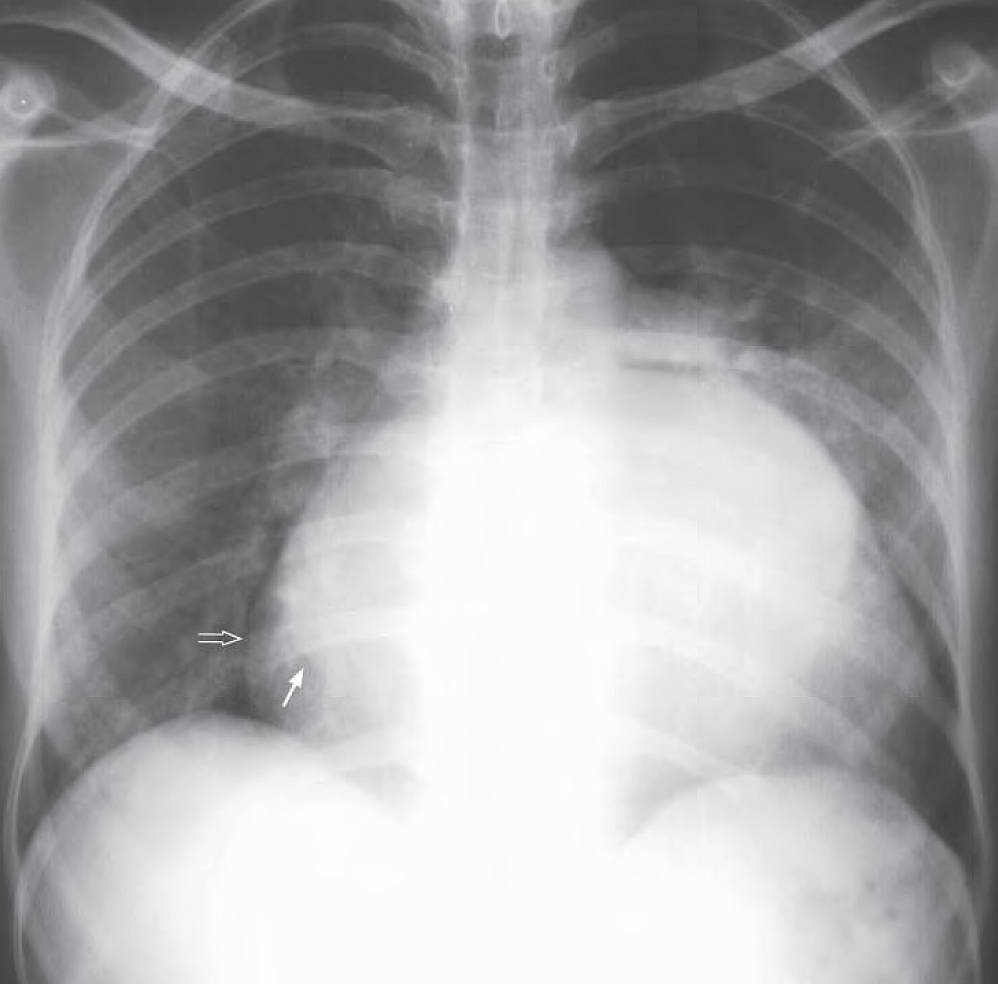

- Cardiomegaly

- Enlarged left atrium seen as a double density (arrow) through the right upper cardiac border (open arrow)

- Prominent pulmonary artery (arrowhead)

- No obvious upper lobe blood diversion or signs of cardiac failure

Diagnosis: Mitral stenosis.

Chest radiograph shows enlarged left atrium with double density (arrow) seen through the right heart border (open arrow) and prominent central pulmonary artery (arrowhead). No radiographic evidence of cardiac failure